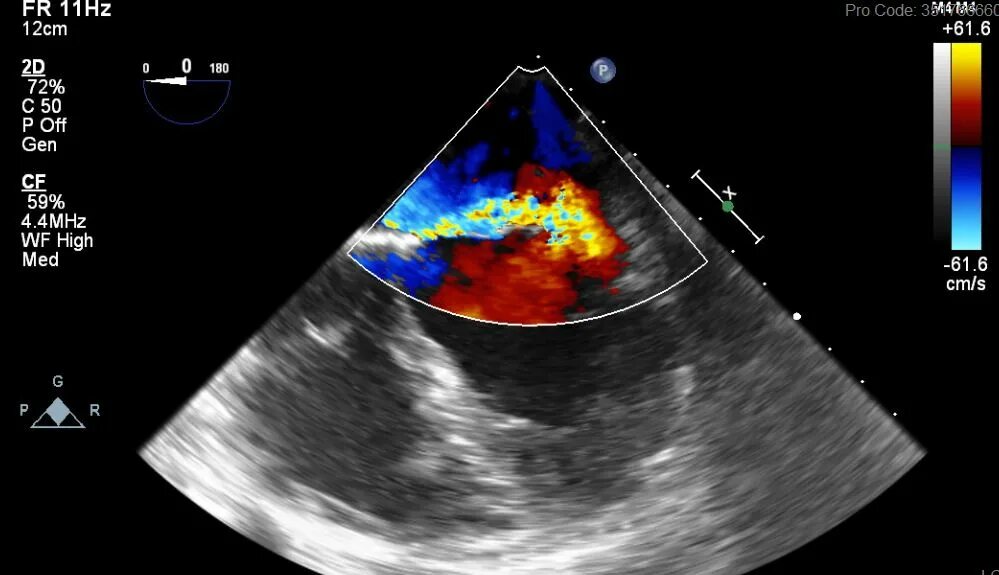

Тромбоз предсердий